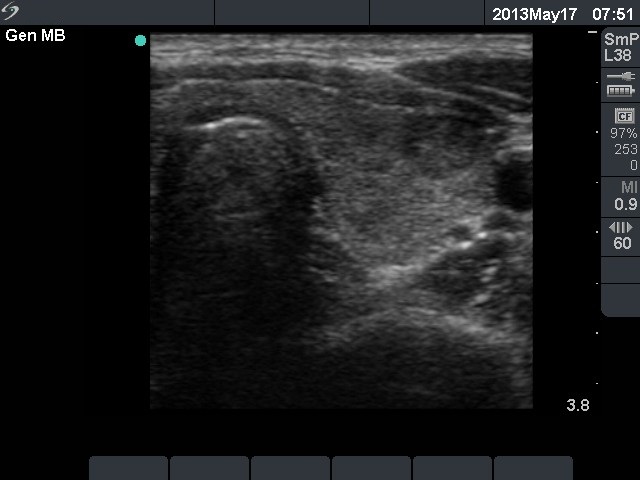

Extrathyroidal spread - case conp 035

Three years prior to present examination (ultrasonographic picture 4)

Left lobe, transverse scan. The lobe presents hypoechogenic areas and a larger nodule-like lesion in the ventrolateral part of the lobe. The latter presents microcalcification.